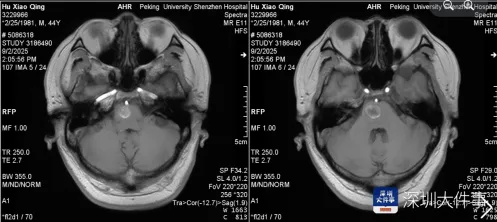

家人紧急将其送往医院,急诊检查结果让所有人揪心——头颅MRI显示,阿伟脑干桥脑右侧存在占位性病变,确诊为海绵状血管瘤并出血。

医生介绍,海绵状血管瘤虽名为“瘤”,实则是异常扩张的血管团,约20%发生在脑干,致死和致残率极高,“每一次出血都可能导致灾难性的神经功能损伤,阿伟的肢体无力和言语障碍,说明出血已经影响到重要神经结构。”